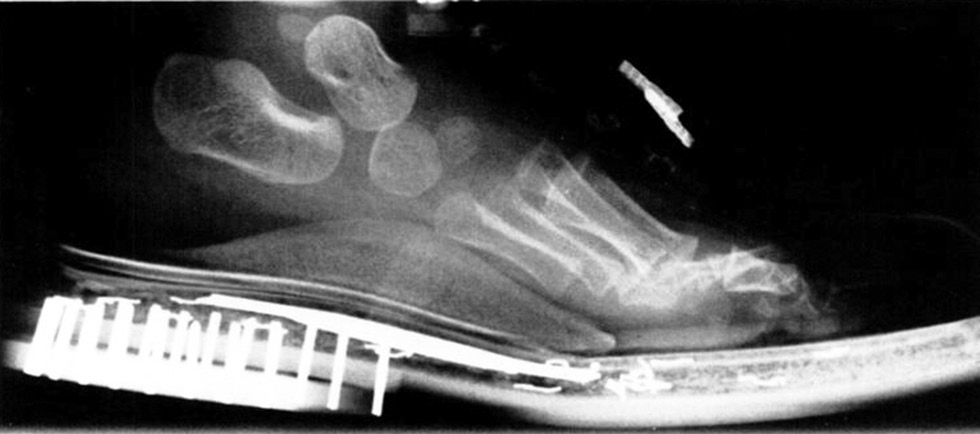

Контрольные рентгенограммы стоп в переднезадней и боковой проекциях в положении стоя в обуви и без обуви выполняли каждые 6 мес. (рис. 4). Пациентов также фотографировали один раз в 6 мес.

Рис. 4. Рентгенография стопы в положении «стоя» в обуви со стелькой UCBL, боковая проекция. UCBL (University of California Biomechanics Laboratory) — Биомеханичеcкая лаборатория Калифорнийского университета